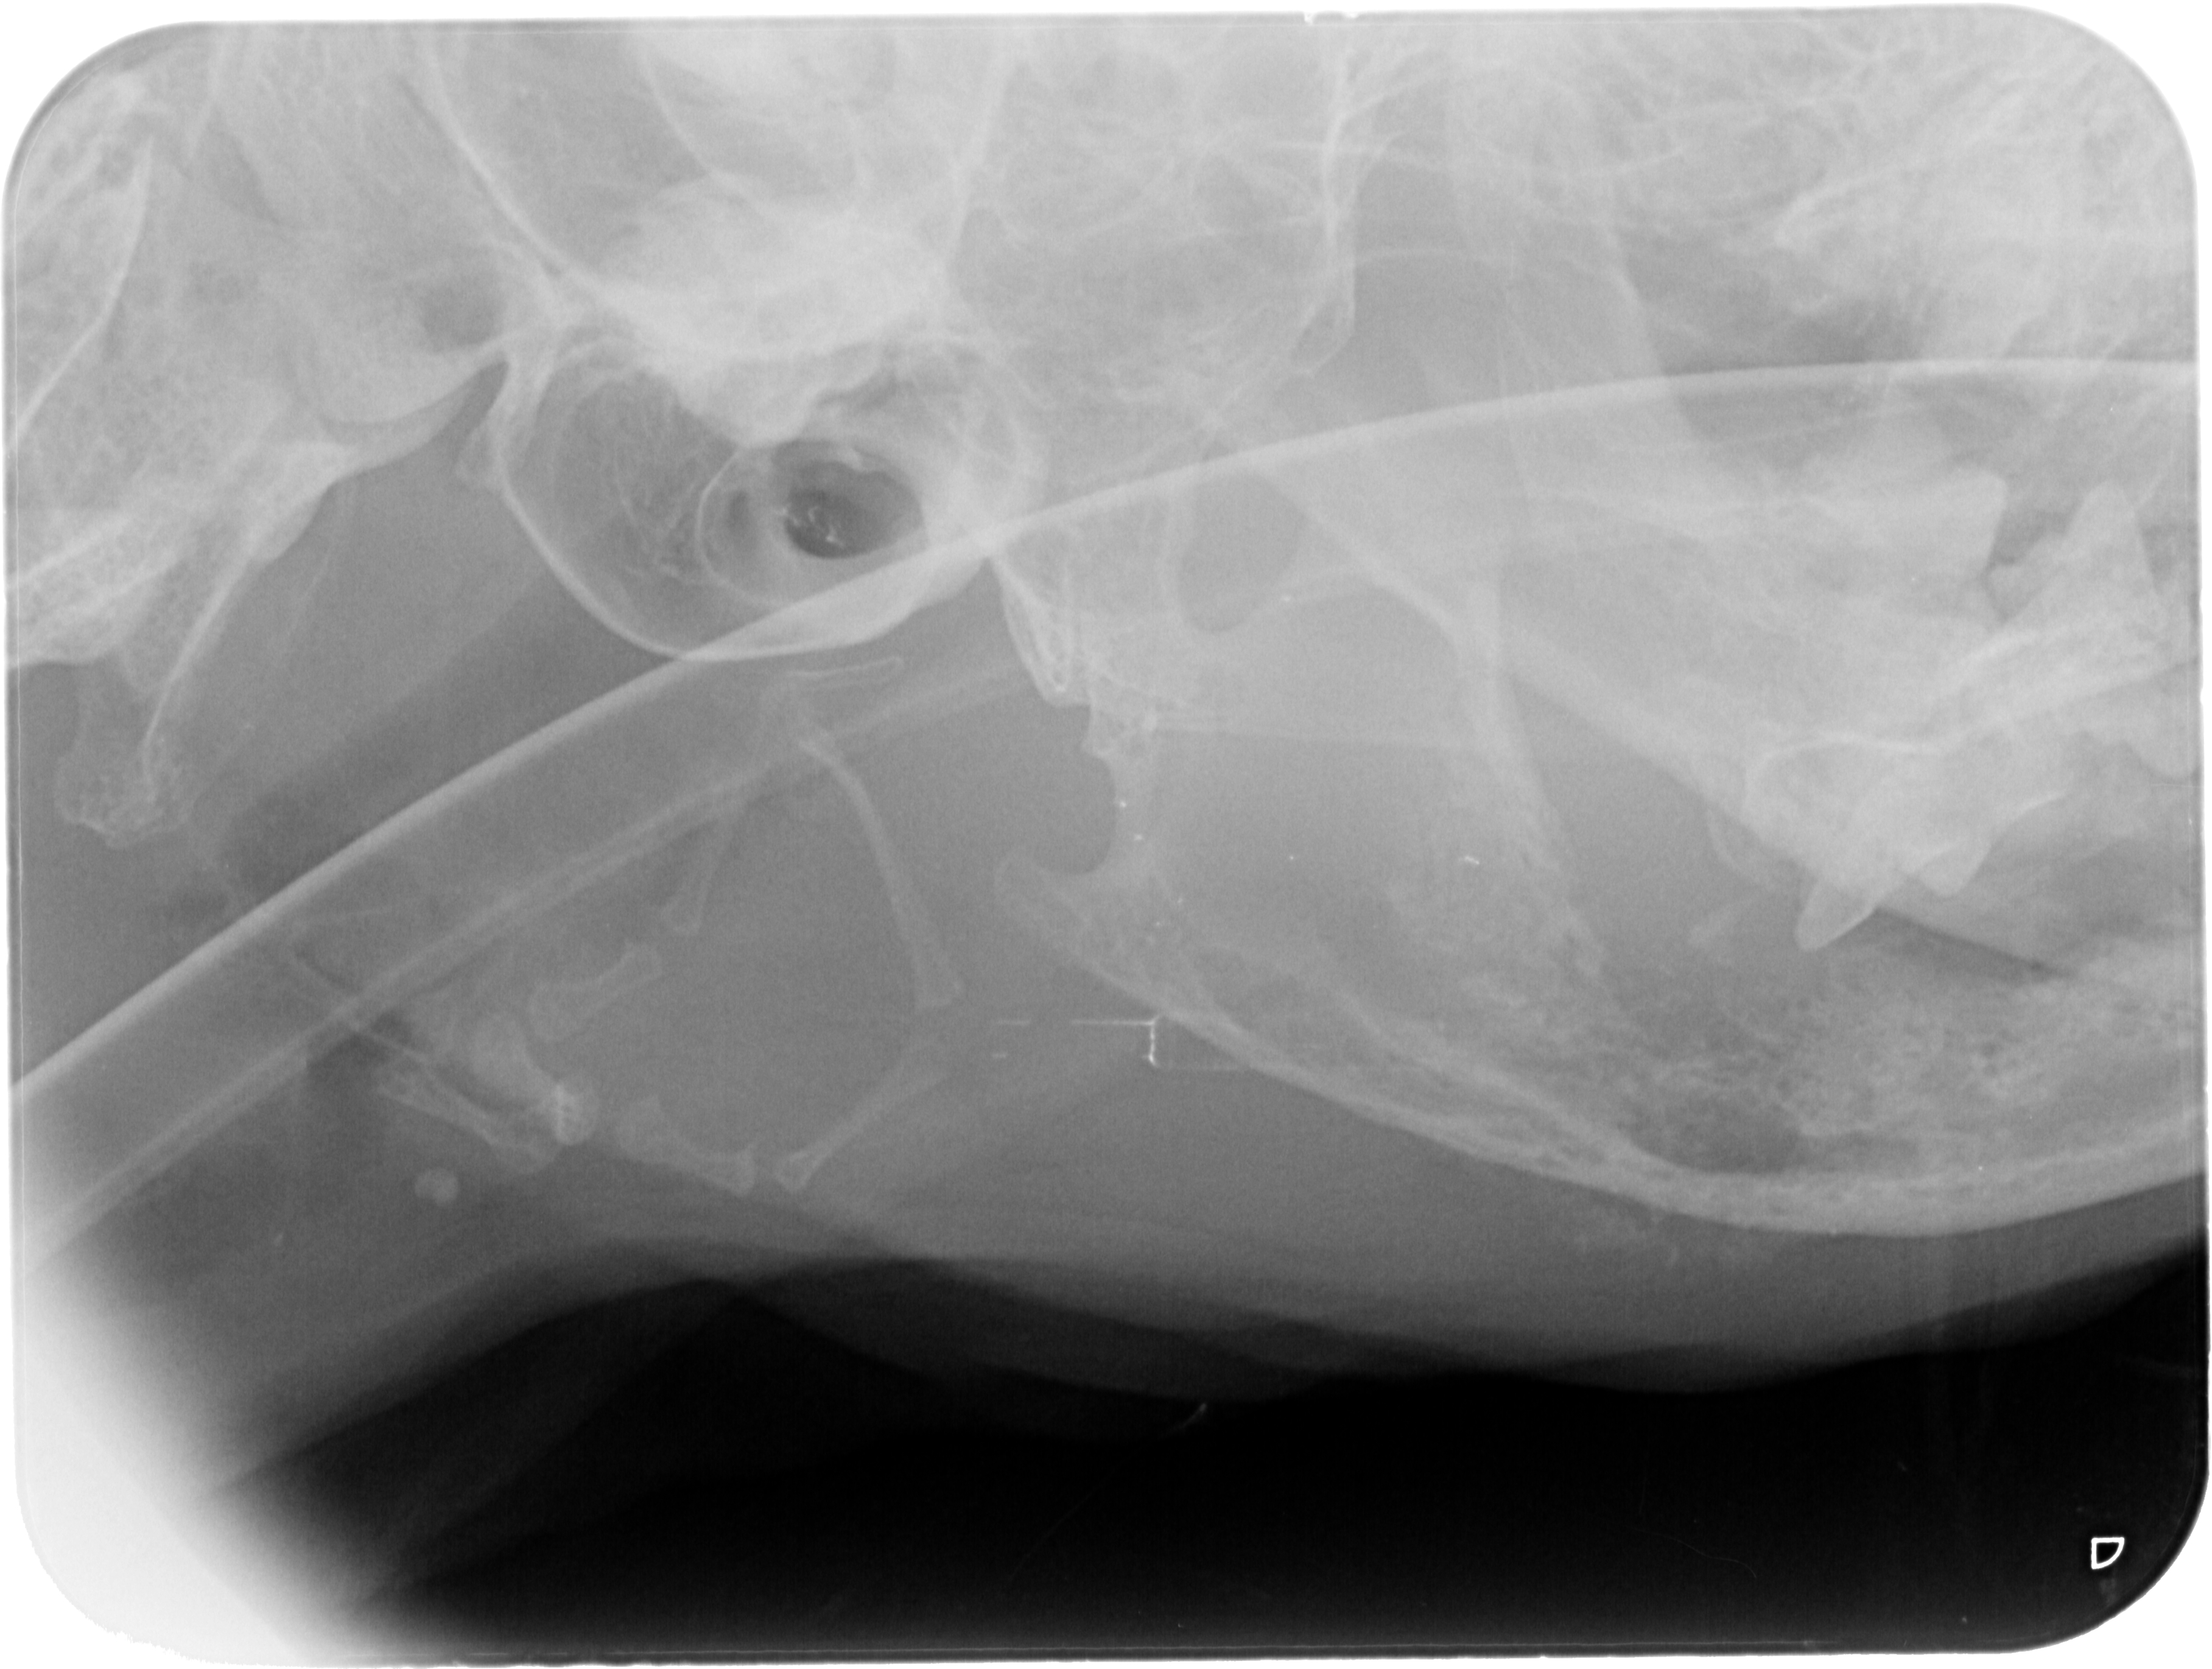

Kæbekræft hos Shana-Mio, 2, 24. januar 2013

Fuld størrelse er

3633 × 2741

pixel